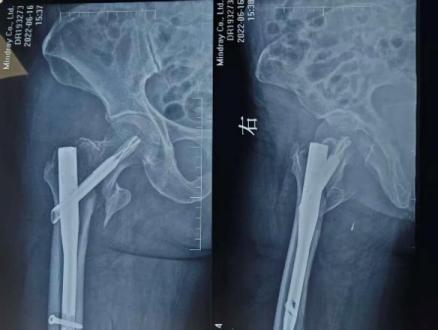

在王争刚主任医师主刀下,手术团队精准取出移位的内固定物,细致处理坏死骨组织,并在骨质缺损区域进行精确重建,最后植入人工髋关节假体。整台手术仅用时1小时,术中出血量少,假体安放位置理想,为患者后续的快速康复奠定了坚实基础。

术后X线片

13天康复奇迹

术后,谈大妈在医护团队指导下开始了系统康复训练。令人欣喜的是,术后第13天,她已能扶着助行器独立行走,疼痛完全消失,髋关节功能得到显著恢复。